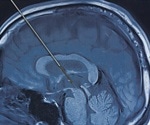

What Does Deep Brain Stimulation Involve?